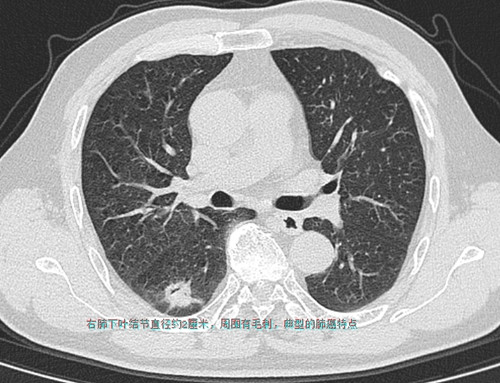

66岁的周嗲嗲家住马王堆,因气促咳嗽在湖南省人民医院呼吸五科住院,胸部CT检查发现在右肺下叶有一个约鹌鹑蛋大小结节,同时在纵膈发现一巨大肿物压迫气管引起狭窄,经胸外科会诊,右肺下叶结节肺癌的可能性非常大,纵膈肿物是颈部甲状腺肿瘤往胸腔内长压迫气管,两个问题都要手术治疗。